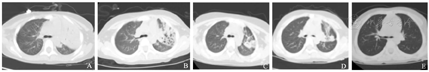

患儿,男,4岁,A :入院时胸部CT示左肺肺炎并肺不张、胸腔积液;B:入院后1周胸部CT示左肺大片状、斑片状密度增高影,可见支气管充气征及多发小囊泡状透亮影,部分支气管扩张,予可弯曲支气管镜术治疗;C:出院后1个月胸部CT示肺炎吸收期,胸腔积液已吸收,左侧背部胸膜局部略厚,肺囊泡影较前基本好转;D:出院后3个月胸部CT示肺炎吸收期,肺囊泡影已消失;E:出院后6个月胸部CT示肺炎已吸收。